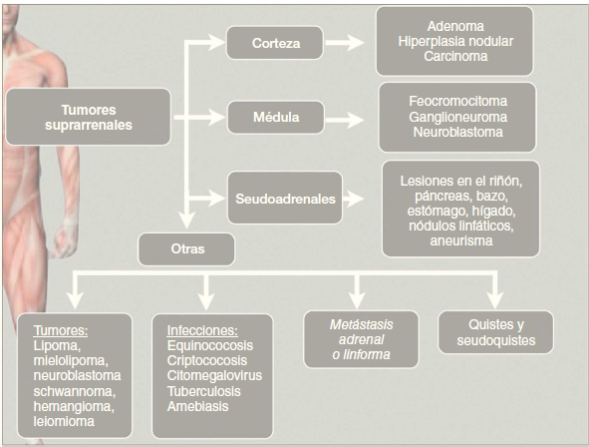

Las posibilidades sobre la naturaleza de la lesión son múltiples: benignas, malignas, funcionales o no, incluso metastásicas (figura 3). Ante el hallazgo, el médico debe tratar de establecer con base en sus características y paraclínicas la potencial etiología pues, a pesar de que en su mayoría son consideradas benignas, algunas pueden tener una degeneración maligna o secretora en su vigilancia. Hasta el 5.7% de las lesiones diagnosticadas incidentalmente son feocromocitomas7.

Figura 3 Tipos de tumores suprarrenales. Basado en Arnaldi G, Boscaro M. Adrenal incidentaloma. Best Pract Res. Clin Endocrinol Metab. 2012;26:405-19.